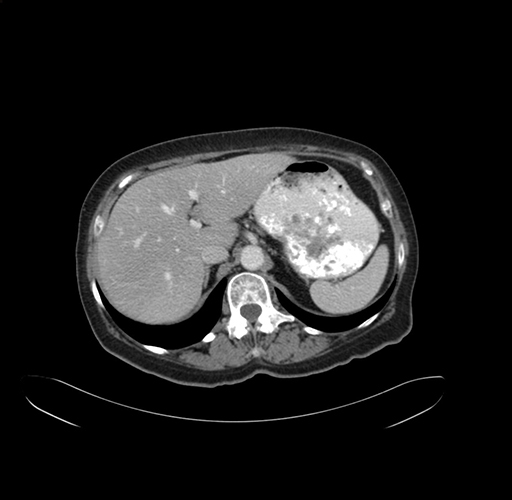

Axial Venous